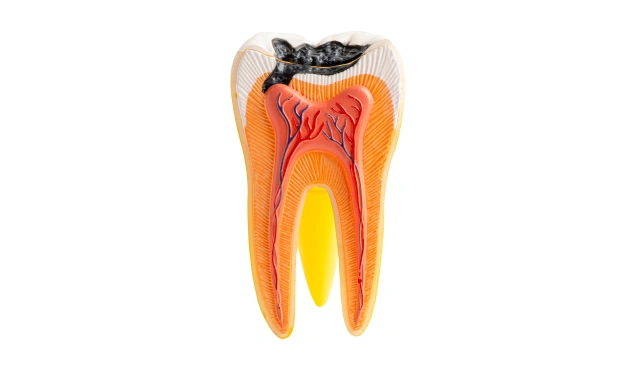

What Is a Root Canal and How Does Tooth Infection Develop?

A root canal is the natural, hollow space inside a tooth that houses nerves and blood vessels. When decay becomes deep, a tooth cracks, or repeated dental work weakens the tooth, bacteria can reach the pulp and cause infection.

• Deep, untreated cavities reaching the pulp